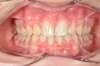

Cas 4 : Description

Chevauchement sévère. Traitement multibague sans extraction.

Avant

Après